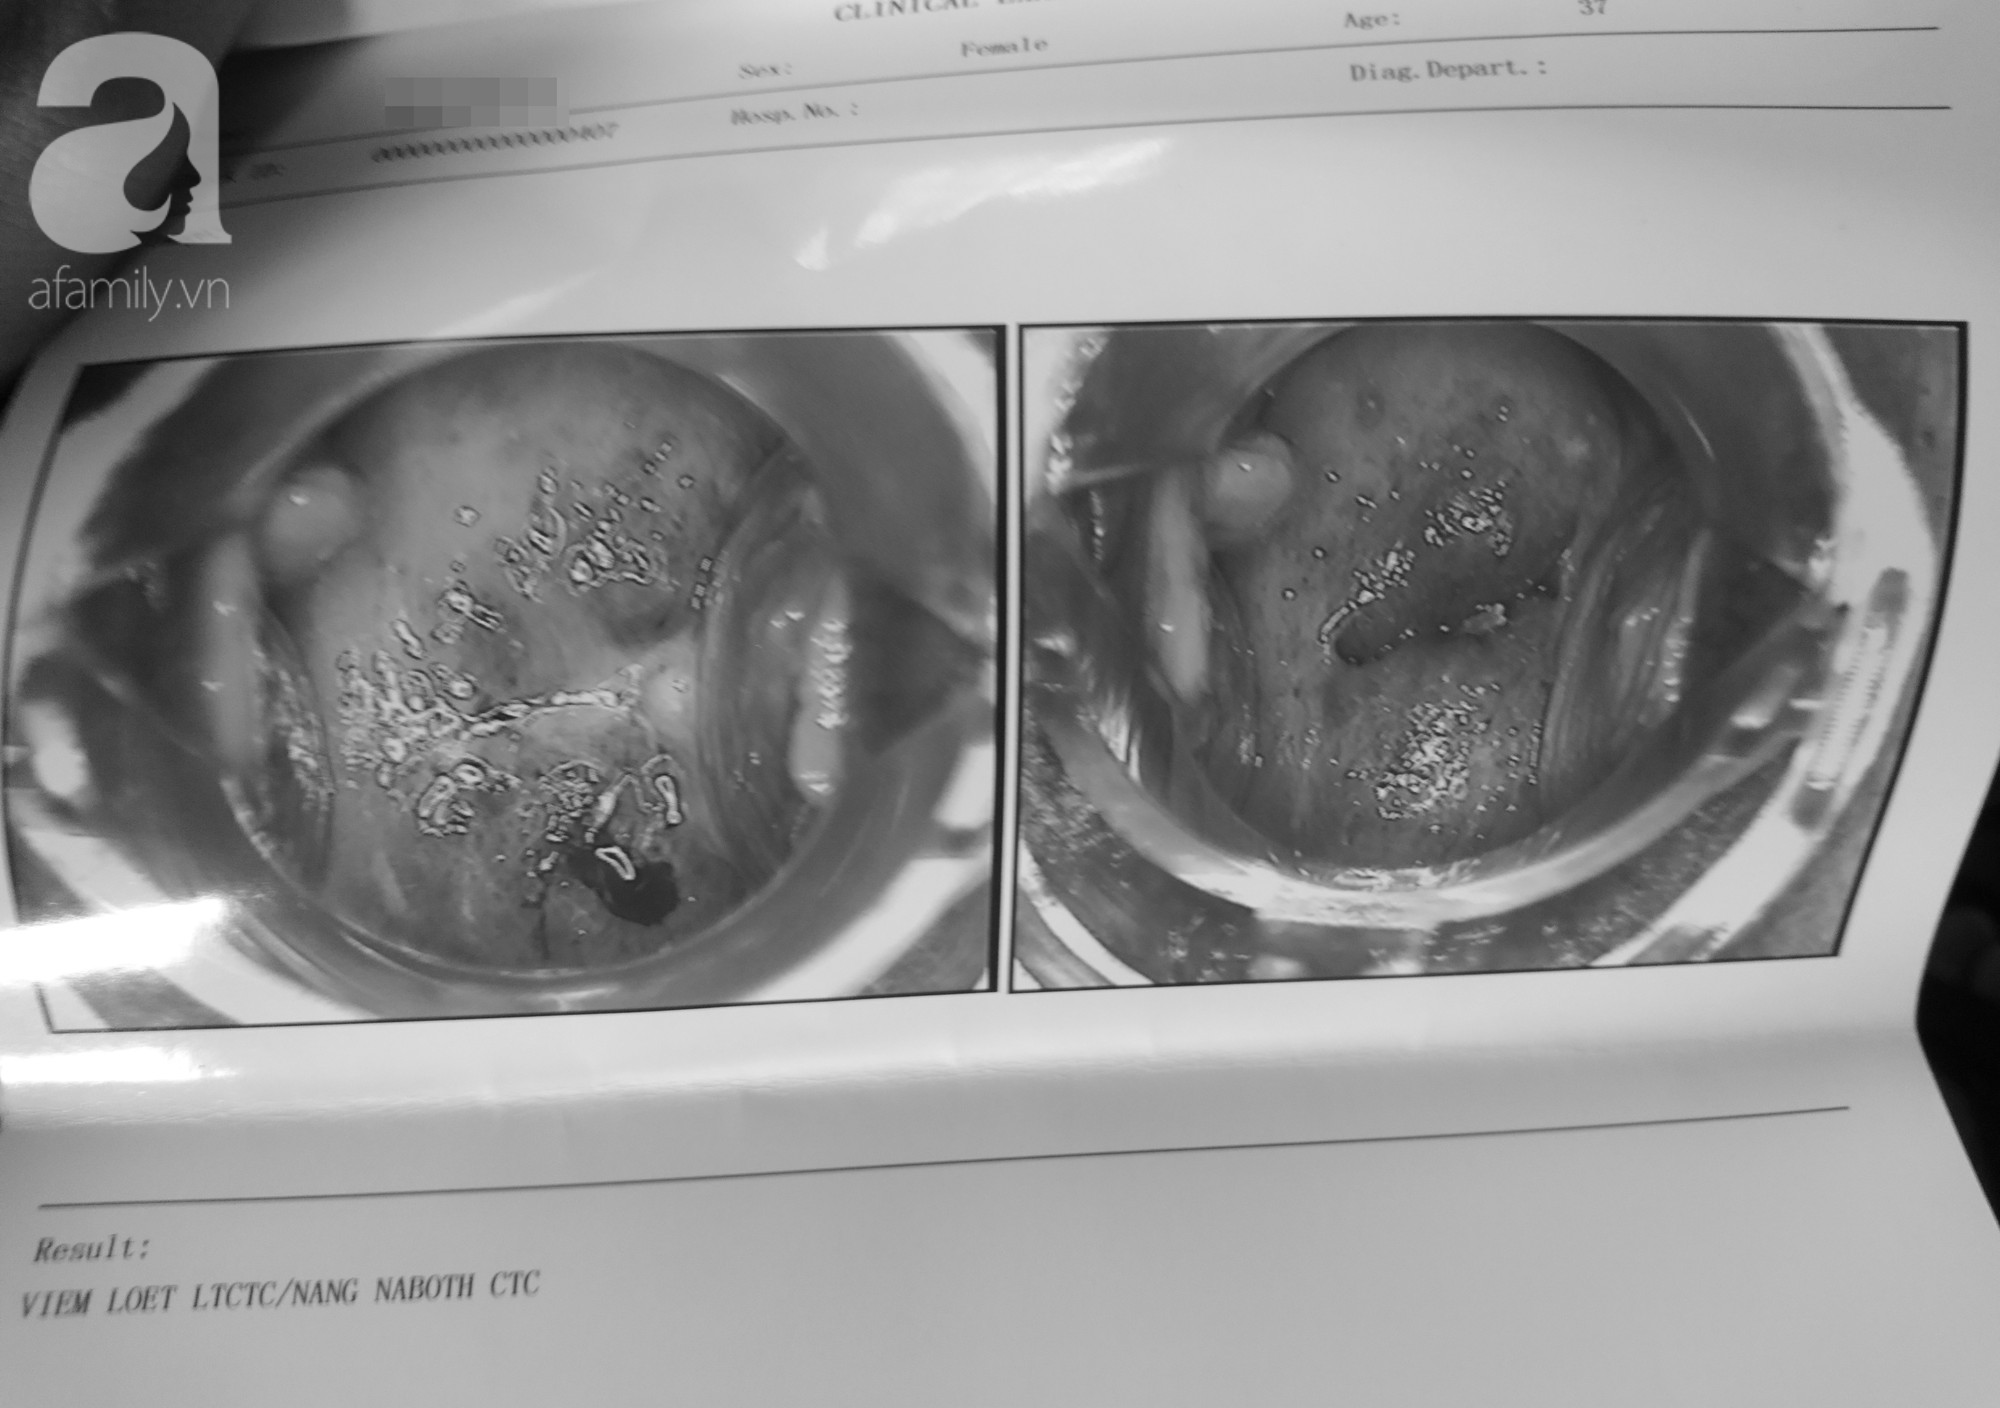

Sau đó một nữ bác sĩ rất trẻ siêu âm đầu dò, dùng máy soi tử cung rồi kêu tôi vào trong phòng. Họ nói rằng tử cung tôi có 2 nang đã hóa mủ và chỉ lên hình để dẫn chứng. Nhìn trên hình có máu nhiều, tôi bắt đầu thấy sợ nên chấp nhận tiểu phẫu để lấy nang với giá 3.89 triệu đồng. Họ chiếu tia gì đó vào vùng kín tôi thấy bốc khói lên, lấy ra hai viên màu trắng và nói đó là nang" – chị L. nhớ lại.

Tuy nhiên mọi chuyện vẫn chưa kết thúc. Sau khi tháo vòng tránh thai và làm tiểu phẫu lấy nang ở lầu 7, một bác sĩ tự giới thiệu sinh năm 1967 nói với chị A. rằng khi kiểm tra phát hiện chị bị viêm loét lộ tuyến cổ tử cung, cần điều trị ngay vì đã nặng.

"Bác sĩ kêu tôi đóng thêm 6 triệu đồng nữa để điều trị viêm lộ tuyến tử cung. Tôi nói vô lý quá, ban đầu sao không phát hiện. Bác sĩ nói là ban đầu khi siêu âm vì tôi có huyết trắng bị che mất nhìn không rõ tử cung, giờ tiểu phẫu xong mới thấy được. Còn người nhân viên ngồi bên cạnh liên tục thúc giục tôi cứ đóng tiền trị dứt điểm đi, đằng nào cũng đã làm tiểu phẫu rồi nhưng tôi không chấp nhận" – người phụ nữ kể tiếp.